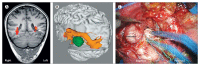

Brain imaging has a crucial role in the presurgical assessment of patients with epilepsy. Structural imaging reveals most cerebral lesions underlying focal epilepsy. Advances in MRI acquisitions including diffusion-weighted imaging, post-acquisition image processing techniques, and quantification of imaging data are increasing the accuracy of lesion detection. Functional MRI can be used to identify areas of the cortex that are essential for language, motor function, and memory, and tractography can reveal white matter tracts that are vital for these functions, thus reducing the risk of epilepsy surgery causing new morbidities. PET, SPECT, simultaneous EEG and functional MRI, and electrical and magnetic source imaging can be used to infer the localisation of epileptic foci and assist in the design of intracranial EEG recording strategies. Progress in semi-automated methods to register imaging data into a common space is enabling the creation of multimodal three-dimensional patient-specific datasets. These techniques show promise for the demonstration of the complex relations between normal and abnormal structural and functional data and could be used to direct precise intracranial navigation and surgery for individual patients.